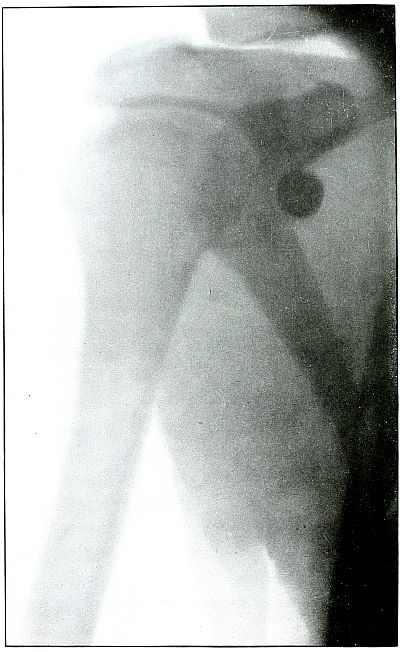

Rifle—Plate 9.

UPPER EXTREMITY.

Gunshot Fracture of the Right Humerus,

with Lodgment of the Missile.

Wound of entrance, antero-external aspect of upper third of arm.

Wound of exit, none.

The missile, deformed by ricochet, struck the bone with greatly

reduced velocity and without sufficient energy to perforate the bone

by which it was deflected slightly from its course and lodged in the arm.

This is something of the same effect that might have been caused by

a shrapnel ball, under the same ballistic conditions with a normal

shrapnel velocity giving about the same penetrating force.

The wound, without infection, is in the first week or two of repair,

before any callus has formed.

Treatment is expectant.

Results favorable.